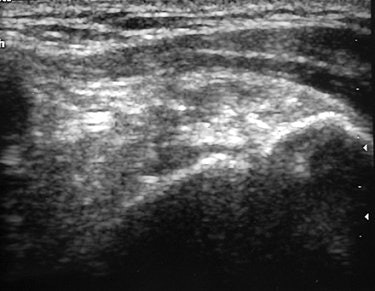

| Same patient as above. Note changes in sonogram of calcification after percutaneous treatment. Ten weeks after treatment, volume of calcification has been considerably reduced and no acoustic shadow is seen. Del Cura JL, Torre I, Zabala R, Legórburu A, "Sonographically Guided Percutaneous Needle Lavage in Calcific Tendinitis of the Shoulder: Short- and Long-Term Results" (AJR 2007; 189:W128-W134). |

At one-year follow-up, post-treatment radiography indicated that 78.1% of the shoulders showed no sign of calcifications. Before treatment, 58.2% of the cases had strong acoustic shadows on sonography, but after one year only 1.6% showed a strong acoustic shadow. A little over half (50.7%) of the shoulders were completely free of symptoms, the authors reported. These patients also reported lower scores on the Shoulder Pain and Disability Index.